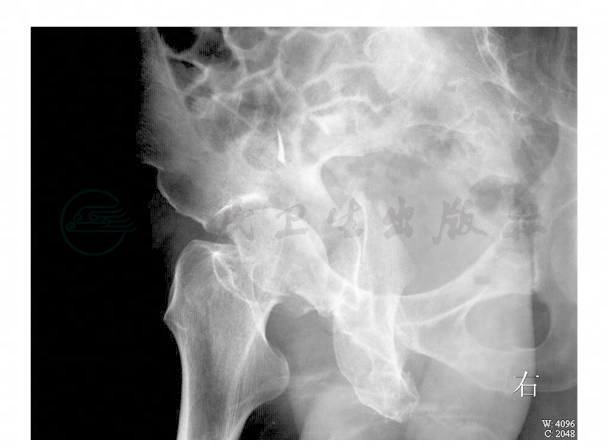

骨盆正位X线片:髋臼骨折(图1)。骨盆髂翼斜位和闭孔斜位X线片:髋臼骨折(图2,图3)。

图2 骨盆髂翼斜位X线片

图3 骨盆闭孔斜位X线片